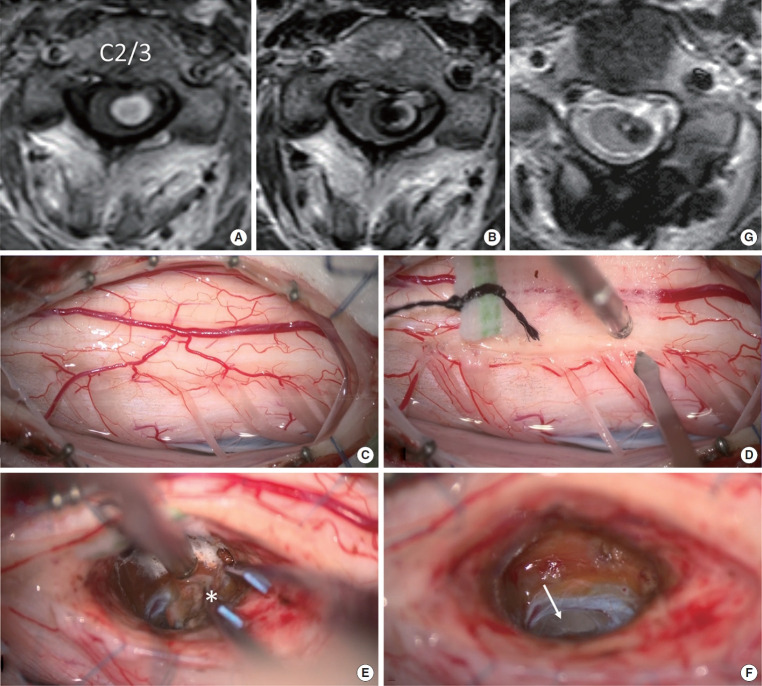

目的:髓内出血(IH)合并高颈海绵状畸形(CM)仍然是神经外科医生面临的一个重大挑战。本研究旨在评估后外侧沟(PLS)入路治疗这些复杂病例的有效性和安全性。方法:本单中心回顾性研究包括近4年来58例经手术治疗的脊髓髓内肿瘤。在IH侧采用PLS入路切除CM。术前、术后一周及最近随访时采用改良的McCormick功能量表(MMCS)评估神经功能。结果:从数据库中确定了6例伴有C3水平以上CM的IH患者。平均年龄31.2岁,女性4例。术前症状持续时间为0 ~ 48个月。所有6例患者均实现了CM的完全切除,未发生包括呼吸系统并发症在内的严重不良事件。平均随访时间为21.7个月。术前MMCS平均评分为3.0分,术后早期维持在2.5分,最近一次随访进一步提高到2.2分。1例腹侧型CM患者在初次手术后30个月在同一水平再次出血。该患者随后接受了第二次手术,采用前外侧沟入路,耐受性良好。结论:PLS入路即使在高颈椎处也能安全切除CM。然而,腹侧型CMs仍然是外科关注的主要问题。

Results: Six patients with IH associated with CM above the C3 level were identified from the database. The mean age was 31.2 years, and 4 of the 6 patients were female. Symptom duration prior to surgery ranged from 0 to 48 months. Total removal of the CM was achieved in all 6 cases without any serious adverse events including respiratory complications. The average follow-up duration was 21.7 months. The mean MMCS score was 3.0 before surgery, maintained at 2.5 in the early postoperative period, and improved further to 2.2 at the most recent follow-up. One patient of ventral-type CM experienced recurrent hemorrhage at the same level 30 months after the initial surgery. This patient subsequently underwent a second surgery using the anterolateral sulcus approach, which was well tolerated.